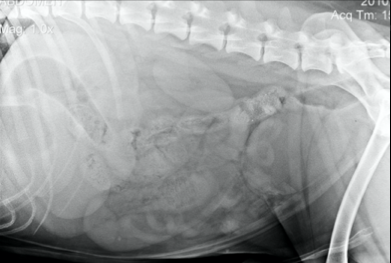

Les techniciens en sueur vous présentent la radio suivante, quelle décision prenez-vous alors?

A) faire l’interprétation de son mieux en expliquant au client nos limitations

B) donner une sédation et reprendre la radiographie plus droite

C) optez pour une contention manuelle et reprendre la radiographie plus droite

D) reprendre la radiographie en doublant le mAs

B)